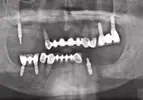

Implant Treatment